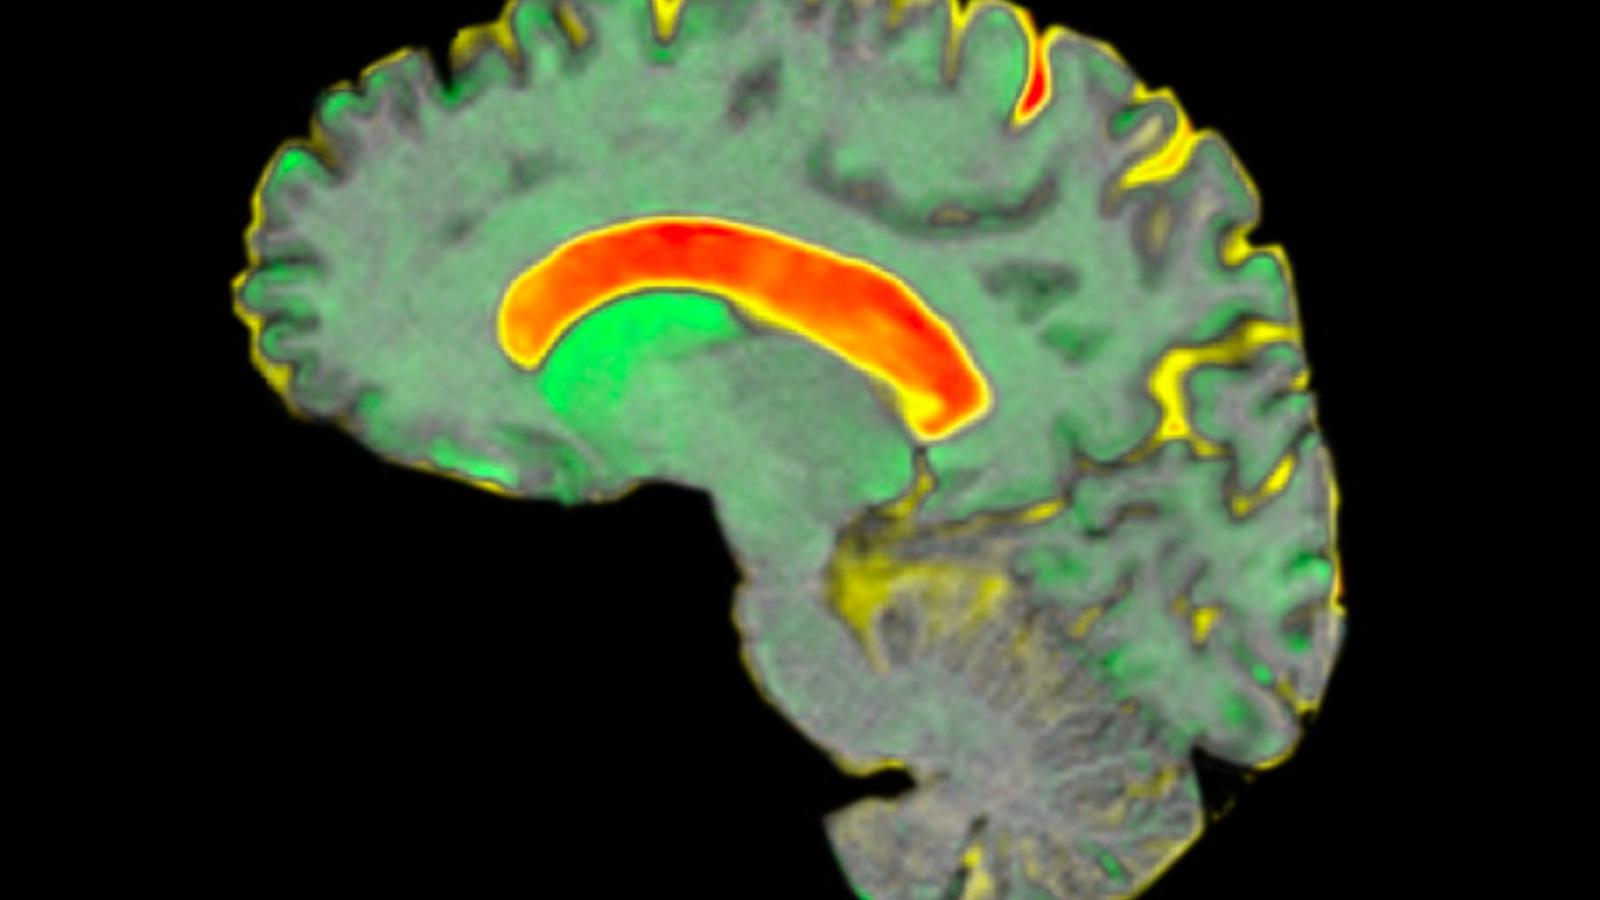

A scan of a huntington's brain

Brain changes in Huntington’s disease occur decades before diagnosis

This study is the first to establish a direct link between somatic CAG repeat expansion, measured in blood, and early brain changes in humans, decades before clinical motor diagnosis. While somatic CAG expansion was already known to accelerate neurodegeneration, this research demonstrates how it actively drives the earliest detectable changes in the brain—specifically in the caudate and putamen, regions critical to movement and thinking.

However, compared to the control group, subtle changes were detected in brain scans and spinal fluid biomarkers of those with Huntington’s disease gene expansion. This indicates that the neurodegenerative process begins long before symptoms are evident and before a clinical diagnosis.